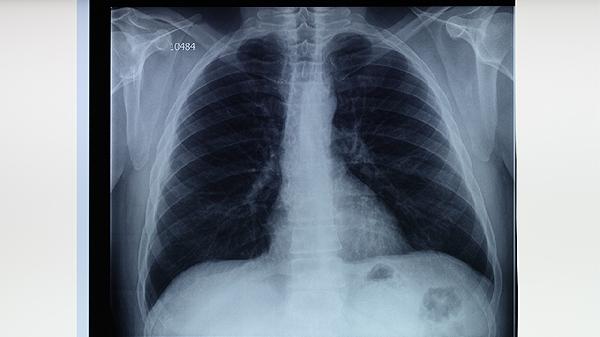

肺結(jié)核的治療原則主要包括早期治療、聯(lián)合用藥、適量用藥、規(guī)律用藥和全程治療。肺結(jié)核是由結(jié)核分枝桿菌感染引起的慢性傳染病,治療需嚴(yán)格遵循上述原則,以徹底殺滅病原體、減少耐藥性產(chǎn)生并降低復(fù)發(fā)概率。

標(biāo)準(zhǔn)治療方案需持續(xù)6-9個(gè)月,耐藥結(jié)核需18-24個(gè)月。即使癥狀緩解也不可擅自停藥,需完成全部療程以徹底清除休眠菌。治療期間每月需復(fù)查痰涂片和培養(yǎng),影像學(xué)評(píng)估病灶吸收情況。完成全程治療可顯著降低復(fù)發(fā)率至5%以下。